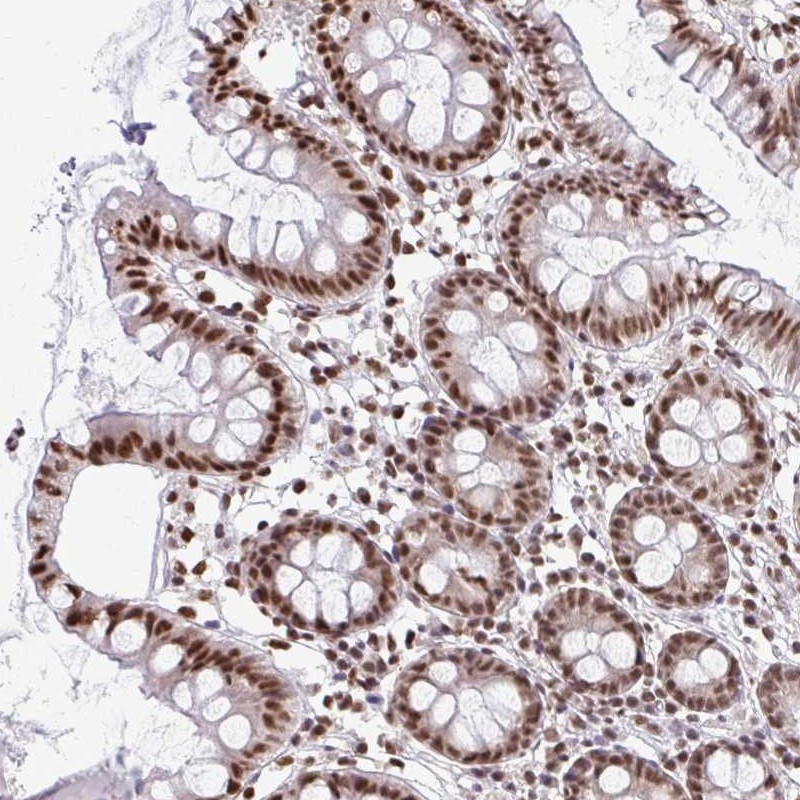

Immunohistochemical staining of human colon shows moderate nuclear positivity in glandular cells.